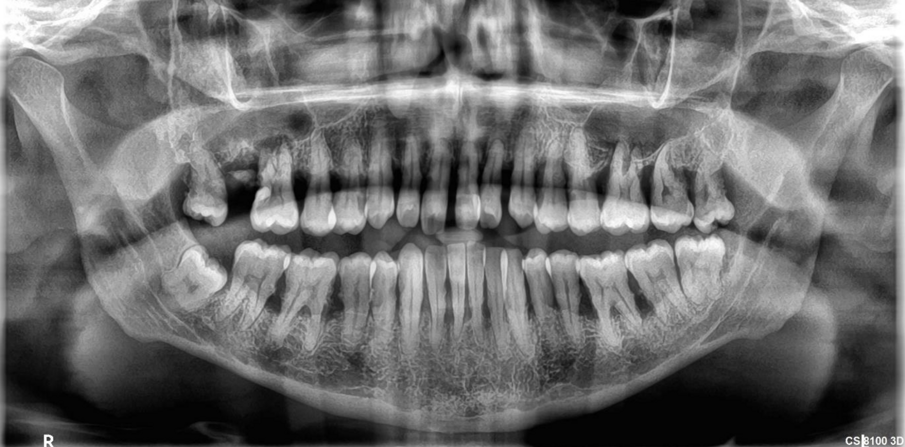

The critical stage of treatment planning is the determination of a tooth’s prognosis. There are several ways of helping with this decision-making – some quite elaborate and expansive taking into consideration both patient factors like willingness and finances and clinical factors like pocket depth, etc.1 Unfortunately, though we make decisions based on bone loss, pocket depth, mobility, etc., —the truth is that the same teeth with the same conditions existing in different patients will have a different prognosis based on hygiene, maintenance, follow-up, masticatory loads, and a certain degree of unpredictability brought in by a wide range of variables that exist at any given time in a patient’s mouth. A clinician’s expertise with regard to both diagnosis and treatment will also determine the success of either treatment. Therefore, following a set flowchart to decide the fate of a tooth is not enough—a clinician needs to bring acumen, experience, something close to intuition, and knowledge of that particular patient to the table. Consolidate all the data and then decide the best course of action.

Even so-called hopeless teeth have been preserved successfully with adequate periodontal treatment followed by strict supportive periodontal treatment (SPT).2,3 Patients with treated aggressive periodontitis have also shown survival of teeth as long as 15 years after treatment.4 This means that patients with seemingly hopeless dentition too could be given the option of holding on to their teeth. They need to be informed that it will just come with a caveat that they must take responsibility for their condition and strictly follow the dentist’s treatment plan and maintenance protocol. At such a time we need to refrain from glamorising the alternative option of an implant—falsely presenting it in a way that suggests that it does not need as much care or that it would last forever. It holds to reason if presented in such a manner 100% of patients who could afford implants, would opt for implants. As soon as an implant is presented as an option it creates a bias in treatment planning as well.5 An implant success rate of 98% and above is misleading as that only refers to its survival in the mouth and not a peri-implant disease, inflammation, or bone loss that afflicts a great number of those surviving implants.6 Therefore, it becomes imperative to present dental implants in a responsible ethical manner—explaining the benefits but also the fact that it is not a fill-it-and-forget-it-situation.

For all patients who opt to save their teeth—the maintenance phase is not just important for the survival of teeth—it is also to ensure no deterioration to a point where it would compromise or jeopardize future implant treatment. We have often in our experience found patients stable for four to six years with regular SPT and suddenly be lost to recall until they turn up ten years later where we are left with no bone to place implants in a conventional manner then resorting to extreme bone augmentation or zygomatic and pterygoid implants. Hence the delicate balance of when saving teeth versus extracting and implants needs to be revisited regularly in each patient to ensure that maintenance of the teeth is not risking the loss of residual bone.